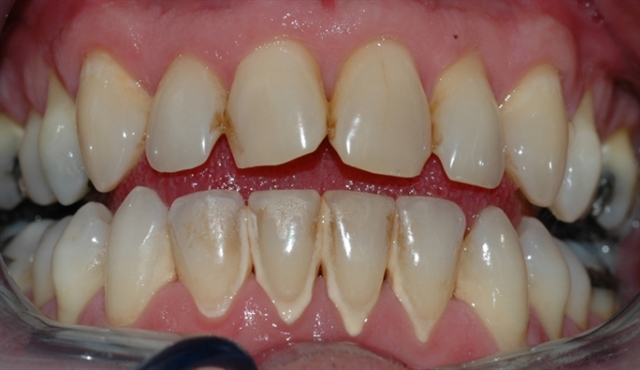

• perio stor 5

perio stor 5

Bildet viser et tannsett med synlig tannsten og misfarging.